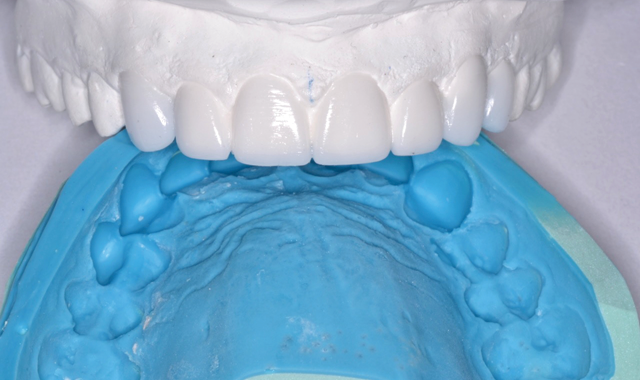

Sally suffered from years of neglect, trauma and abuse. Her teeth were a disaster, but her life was turning around, and she wanted to save her smile and regain her self-confidence (Fig. 1).

Traditional treatment options would be full-mouth reconstruction (FMR) or full-mouth extractions and dentures. FMR would require numerous root canals, build-ups and porcelain restorations, but with limited finances, this was not possible.

Fig. 1 Fig. 2